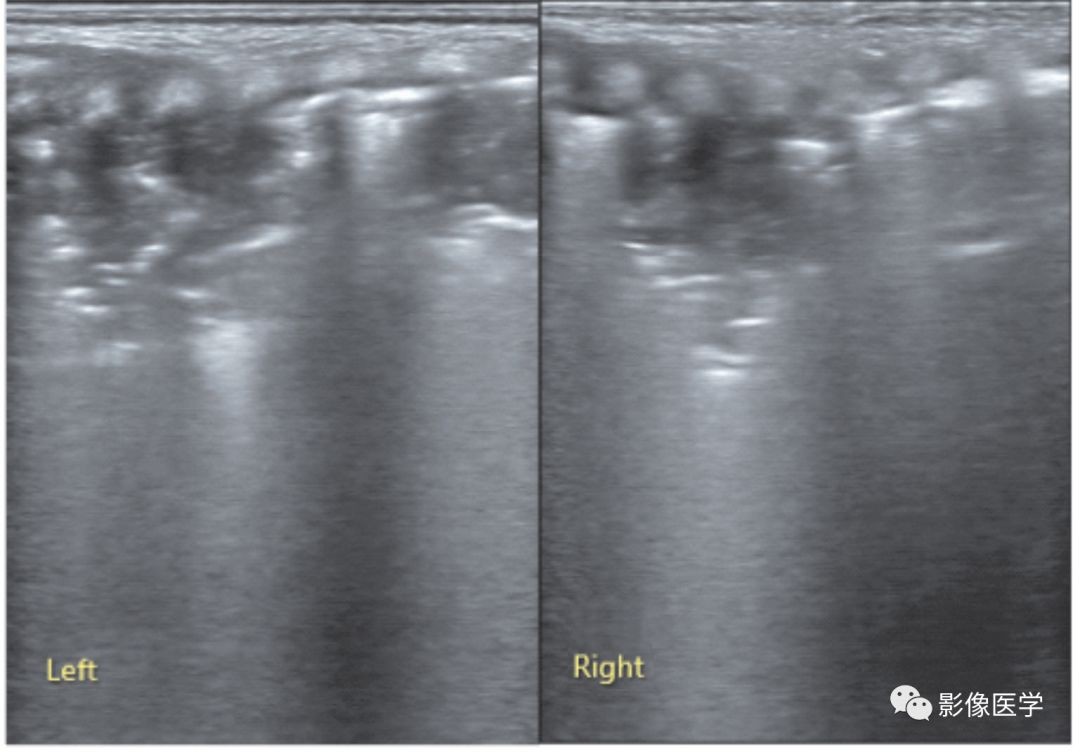

图6-28 轻度肺炎的超声表现:胸膜下局灶性实变

肺脏超声(探头与肋间隙平行扫描)可见两处局限于胸膜下的小范围实变,实变程度与炎症程度有关,肺炎时不一定都会有大面积实变,轻度肺炎时实变范围可以很小。探头与肋间隙平行扫描时,往往更有助于发现局限于胸膜下的小实变。